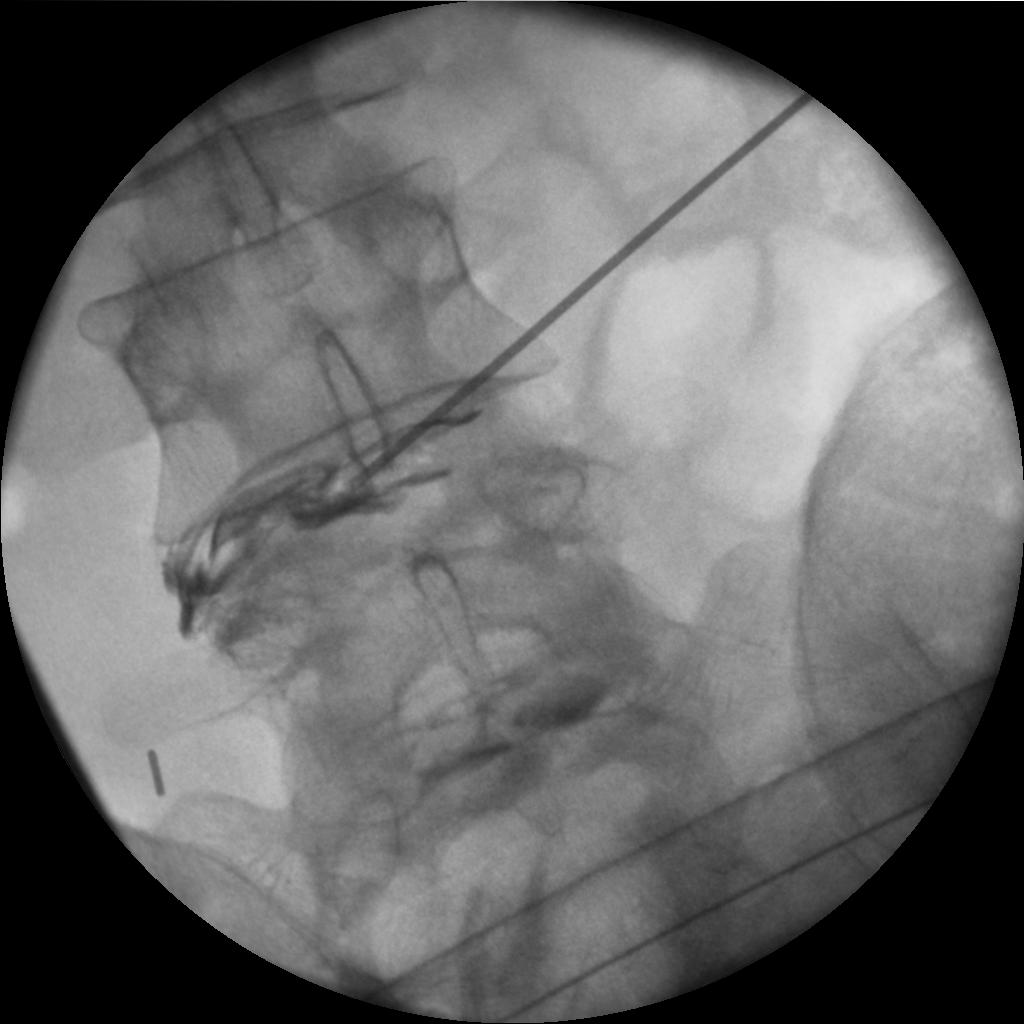

The left-hand image shows a HIZ at the left side of disk L4/5. This would fit the fact that I have strong pain on the left side of my back, going down into my leg, but not beyond the knee.

The second image here shows a HIZ at the back-side of the L3/4 disk. This led at least me to hypothesise that this was the disk that ruptured already in August.

The medical director and my uncle got together over the weekend to discuss my case. For some reason, the medical director hadn't remembered that all my pain was on the left side. When he realised it, all the pieces fell into place. The above X-ray images of the discography show that while the contrast media stayed inside the L3/4 disk, it escaped to the left from L4/5, indicating a completely ruptured disk. Moreover, as a result of the leak, it was not possible to build up the pressure needed to produce my normal back pain, so this explained the initially negative finding.

Once again, the needle was inserted into my back and into my L4/5 disk. The first attempt to place the thermal catheder failed as it landed it the wrong place inside the disk (see the first image on the left). Pushing it in and pulling it out was no fun - a very peculiar pain inside my disk which I have never experienced before and hope to never experience again.